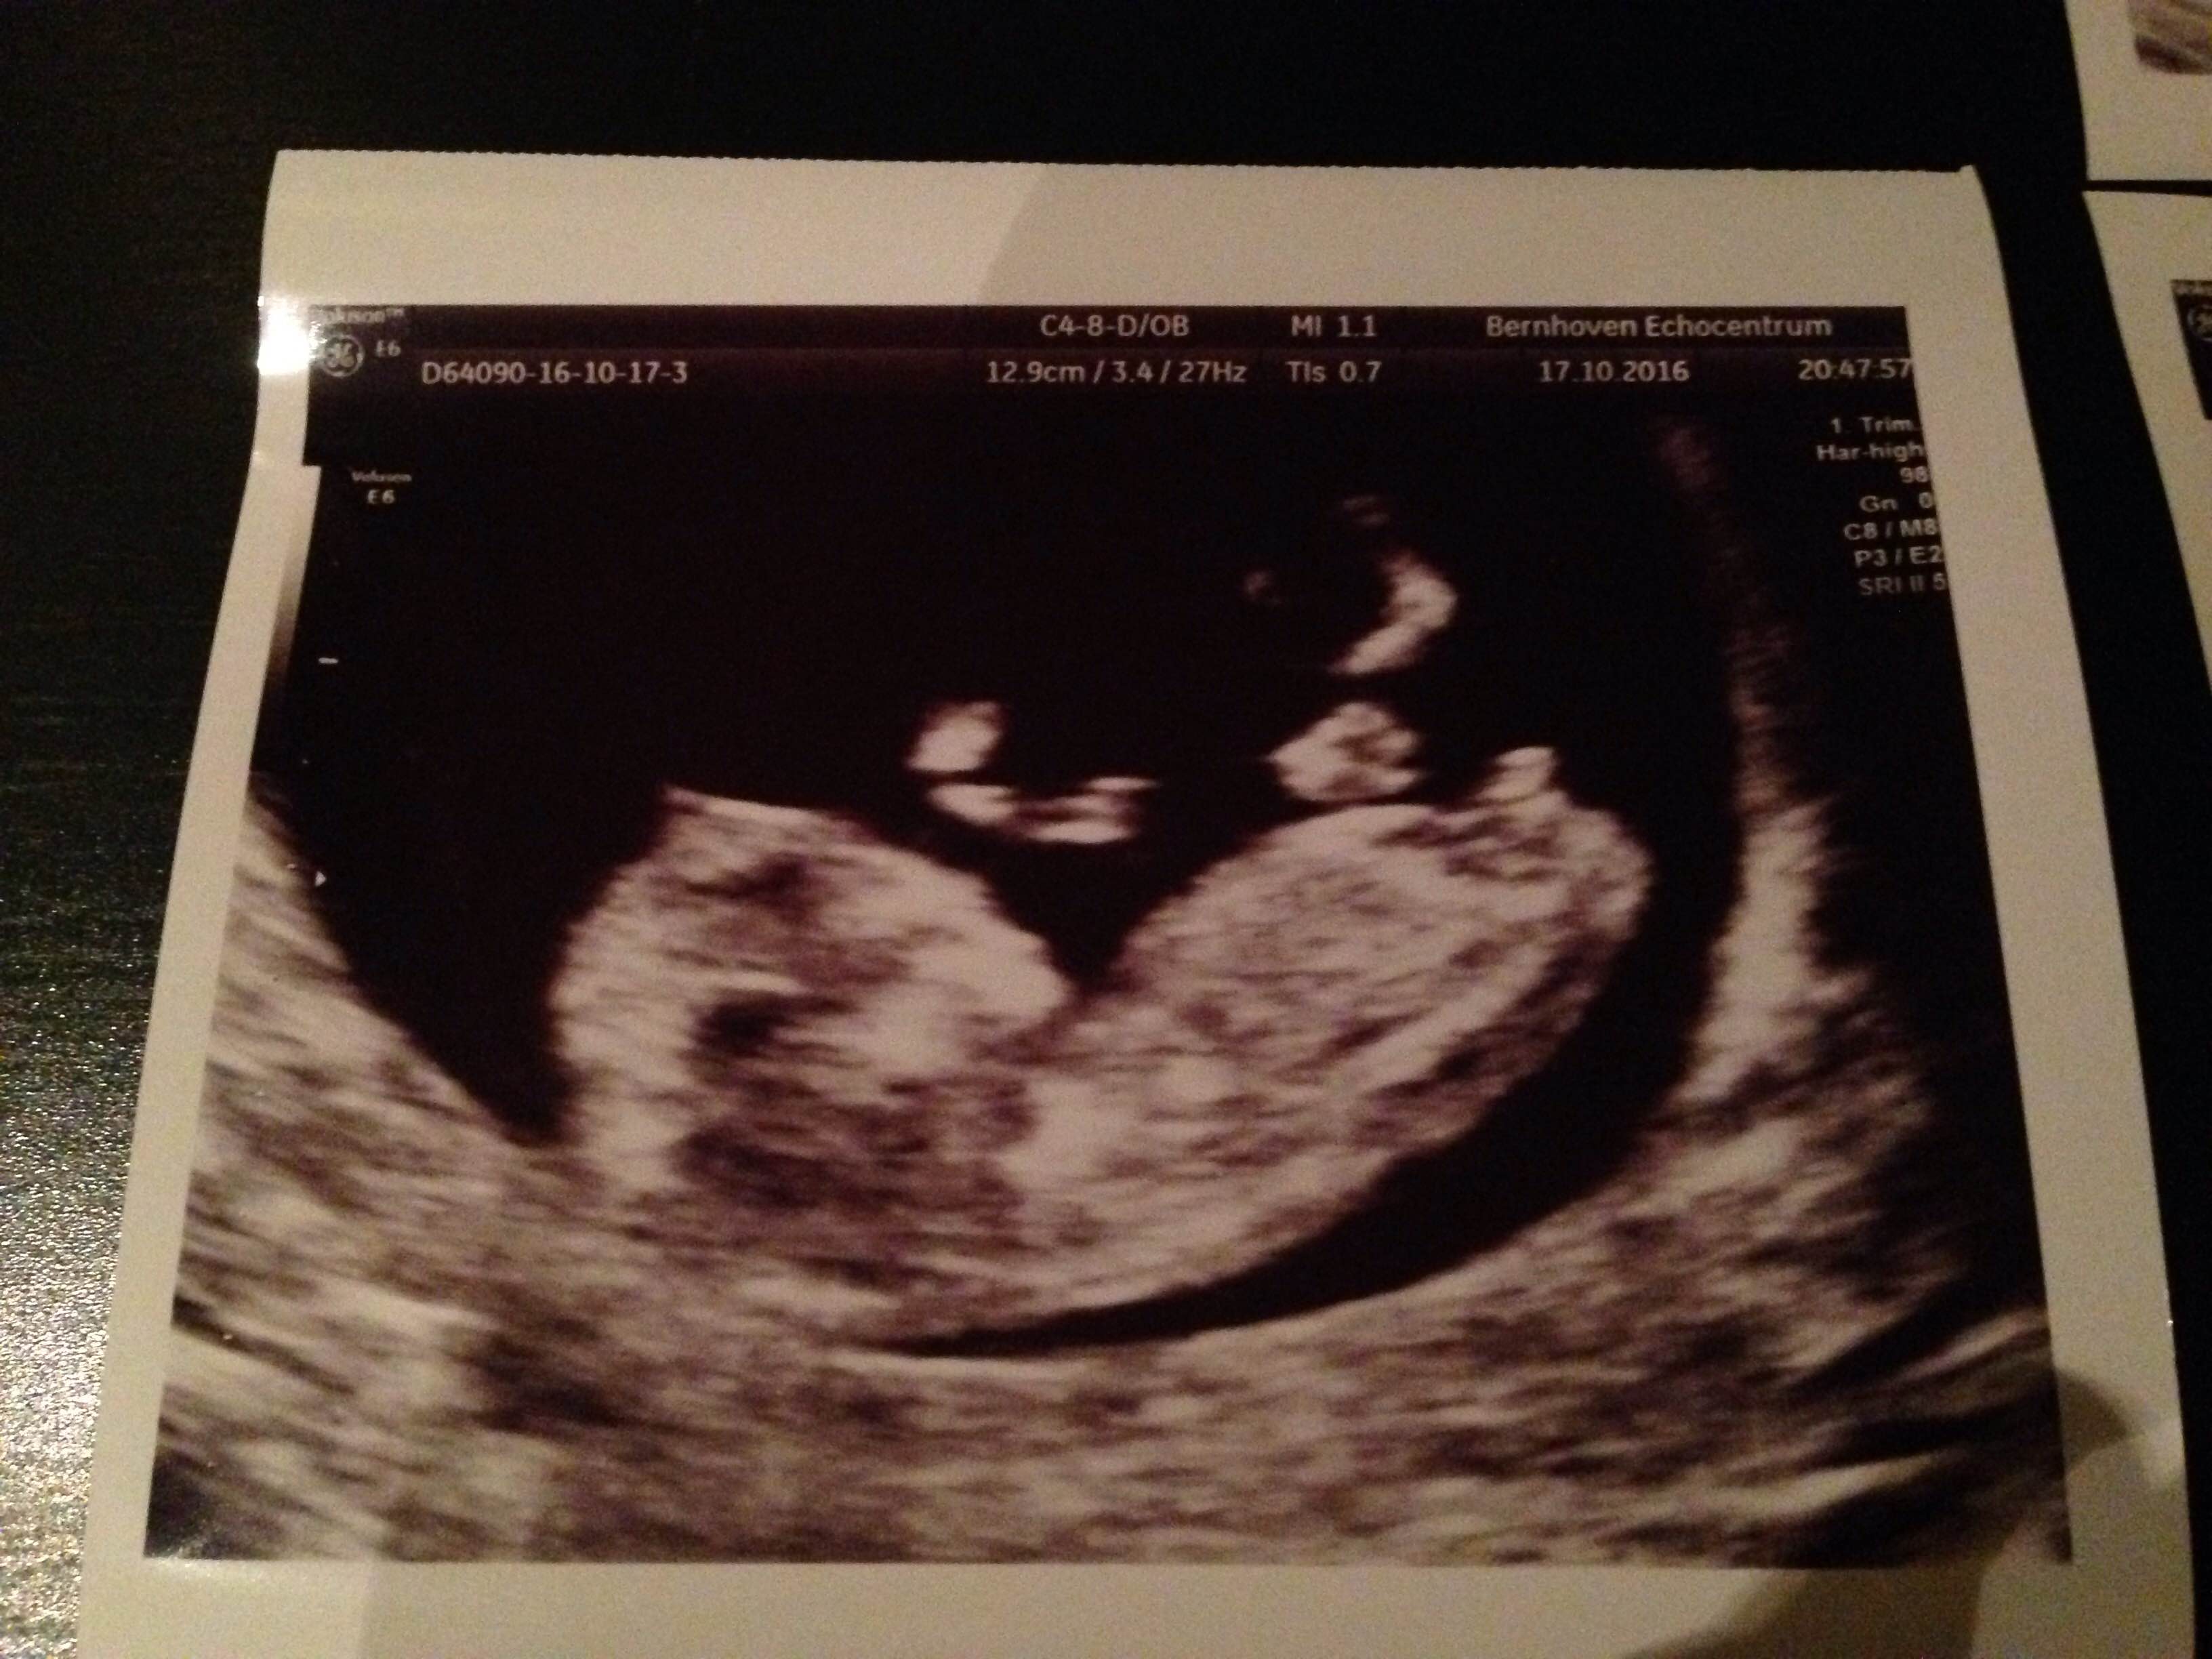

The first two photos are from 11w + 4d, the last one 11w + 6d.

I am so excited to find out, what do you think pink or blue?

Attachment 33456Attachment 33457Attachment 33458